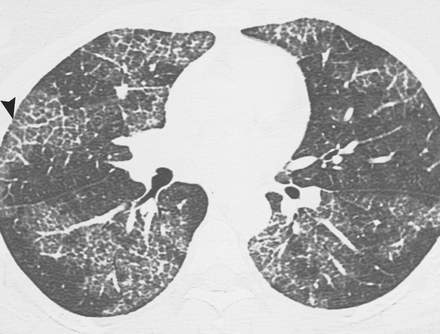

Usual Interstitial Pneumonia

Fx on HRCT:

DDx: